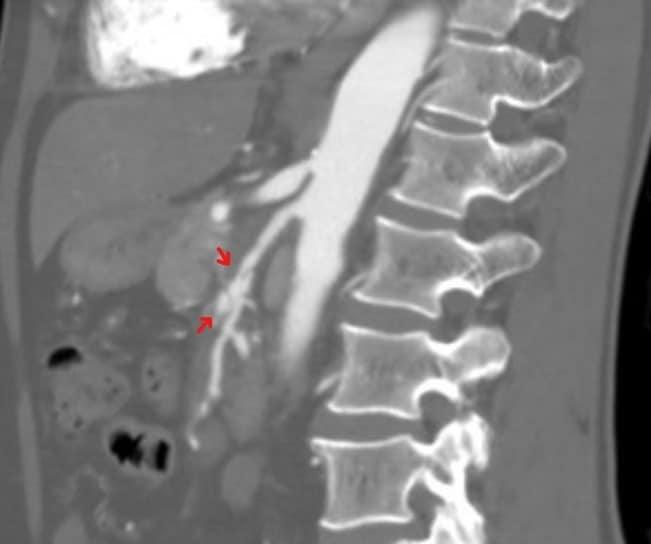

Segmental arterial mediolysis should be diagnosed with pathology. A pathological specimen will show vacuolar degeneration of the smooth muscle in the outer media that results in gaps in the arterial wall, leading to aneurysms and dissections. In modern practice, segmental arterial mediolysis is suggested on imaging. CT is the most common modality. The lesions appear as strands of arterial narrowing. CT can also detect complications including dissection, aneurysms and organ infarct. Please note that I wrote that imaging can only suggest the diagnosis. Without pathology, other arteriopathies are possible.